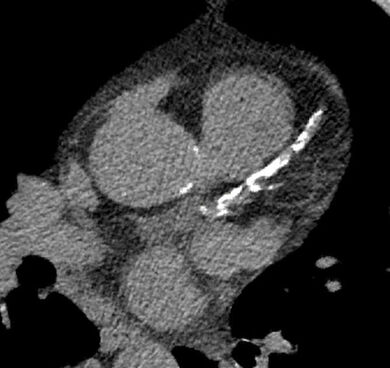

Die anatomische Darstellung der Herzkranzgefäße sowie der großen Herznahen Gefäße sind elementarer Bestandteil der kardiologischen Diagnostik und entscheidend für die Therapieplanung bei Patient*innen mit Brustschmerz. War früher die invasive Koronarangiographie die einzige Möglichkeit die Herzkranzgefäße zu untersuchen, ist nun das Kardio-CT mit gleicher diagnostischer Sicherheit etabliert und weltweit in den Leitlinien empfohlen.

Alternativ oder ergänzend können mit dem sogenannten Calcium-Scoring unter geringer Strahlendosis und ohne den Einsatz von Kontrastmittel Verkalkungen der ausgeschlossen werden.

Neben Diagnostik bei stabilem Thoraxschmerz, hilft die CT-Angiographie auch in der Akutdiagnostik. So können neben Engstellen an den Herzkranzgefäßen auch andere, potentiell lebensbedrohliche Erkrankungen wie Lungenarterienembolien oder Erkrankungen der Hauptschlagader (beispielsweise eine Aortendissektion) im Rahmen einer einzigen kontrastmittelverstärkter CT Untersuchung zuverlässig ausgeschlossen werden. Ein weiteres auf Grund des technischen Fortschritts der invasiven Kardiologie immer wichtiger werdendes Feld ist die CT-Angiographie zur Planung komplexer interventioneller Herzklappeneingriffe (z.B. vor transfemoraler Aortenklappenimplantation).

In Kooperation mit der Klinik für diagnostische und interventionelle Radiologie führen wir ambulante und stationäre Kardio-CT-Untersuchungen an zwei hochmodernen CT-Geräten (Philips IQon Spectral CT und Siemens Somatom Force) durch. Wir sind zertifiziertes Zentrum der deutschen Gesellschaft für Kardiologie und haben seit vielen Jahren Erfahrung in der Durchführung.